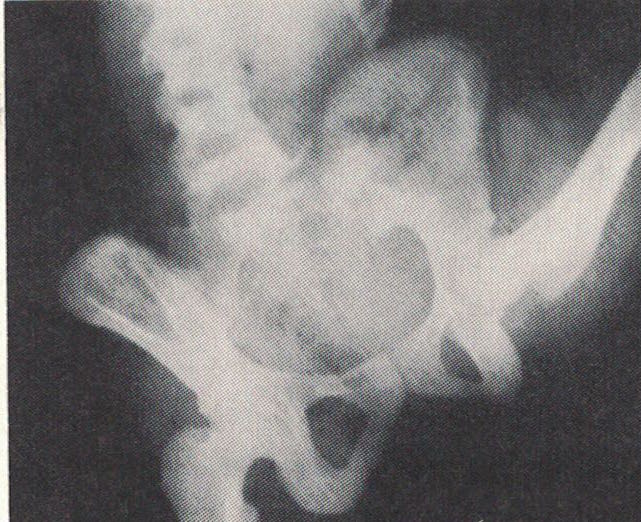

Fig. 3.16

In questa radiografia, realizzata mentre la danzatrice si trova con la gamba destra à la seconde (gamba libera sollevata di lato), osserva l’inclinazione laterale del bacino verso la gamba portante. Questa inclinazione favorisce l’elevazione della gamba libera oltre i 90 gradi. Osserva anche come la colonna vertebrale formi una curva concava dalla parte della gamba libera. Questo ti fa capire come le parti del corpo siano tra loro tutte interdipendenti (C. Sparger, "Anatomy and Ballet", 1970).